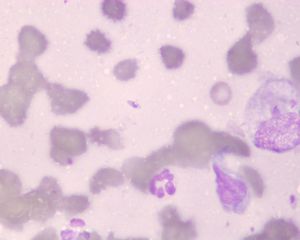

Leishmaniose (Hautabklatsch, Hund)